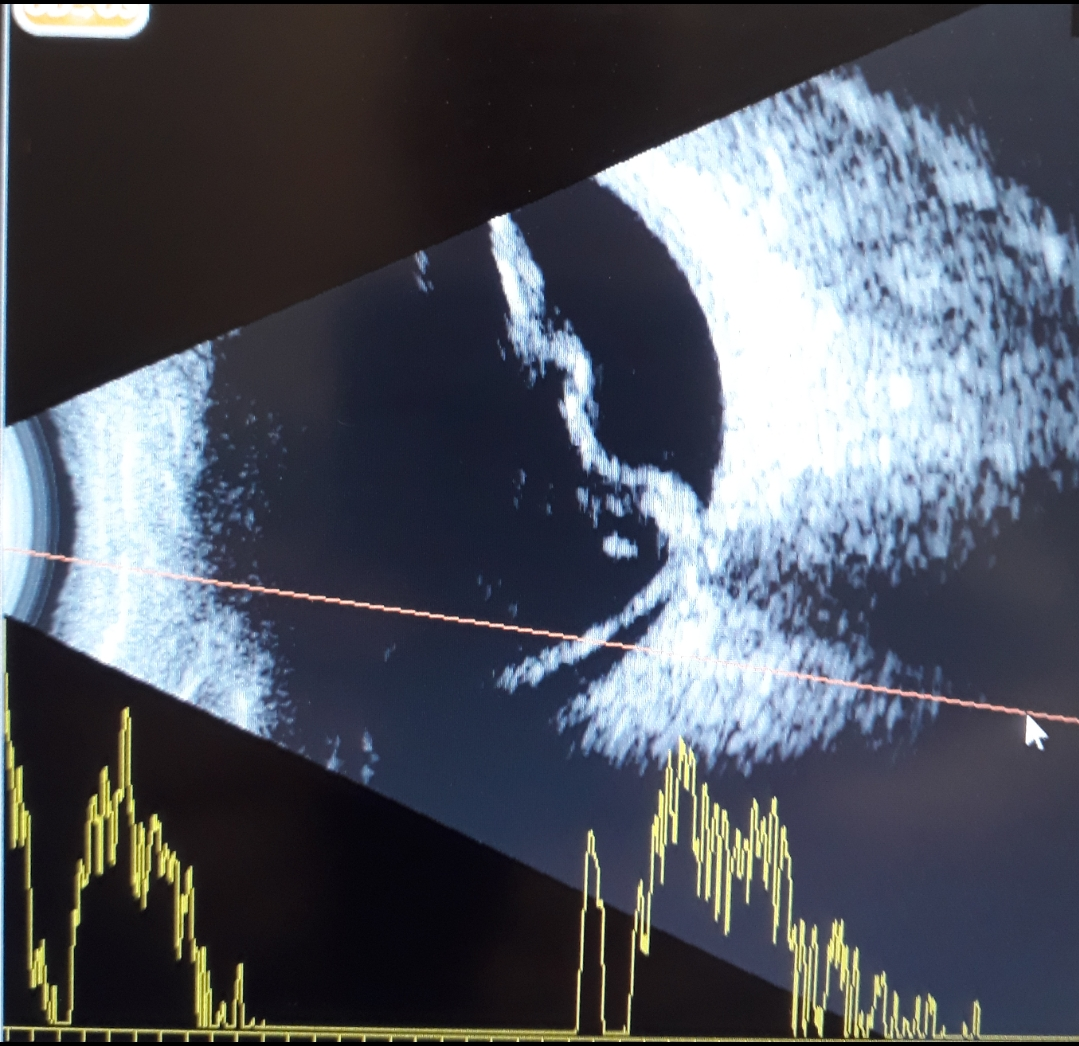

Göz ultrasonografi veya göz ekografisi gözün ön ve arka kısmının değerlendirilmesini sağlayan çok önemli bir muayene yöntemidir. Optik ortamın bulanık olduğu durumlarda ultarasonografi ile göz yapılarının değerlendirilmesi yapılarak gözdeki hasarın derecesi belirlenir. Gözde genellikle A ve B mod ultrasonografi kullanılır.

B mod ultrasonografi özellikle göz arka kutbunun hastalıkları için kullanılır. B mod inceleme kapak üzerinden veya göz yüzeyi üzerinden yapılabilir. B mod probu göz yüzeyinde gezdirilerek göz arkasındaki hastalıklar incelenir. Retinanın göz duvarından ayrılmış olup olmadığı ayrıca vitreus boşluğunun durumu değerlendirilir. Ultrasonografi ile muayenenin sonunda göz hekimi veya radyoloji uzmanı göz arka duvarındaki bir çok patoloji hakkında fikir sahibi olur ayrıca ameliyat yapılacak ise en uygun strateji belirlenir.